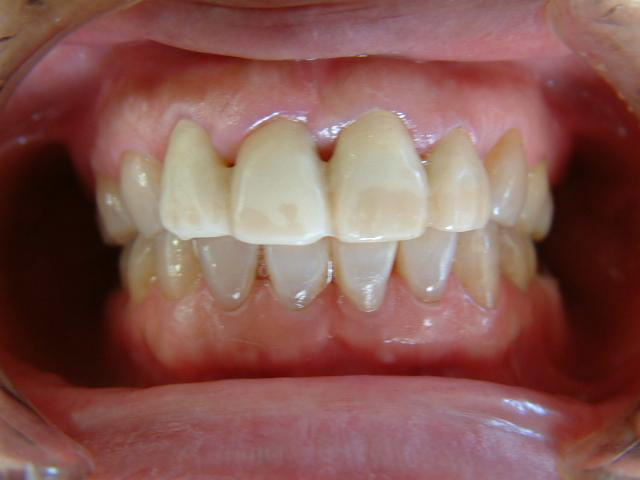

初診の状態とセット時の状態

初診と最終補綴物

患者さんにも満足して頂けた最終補綴物 |